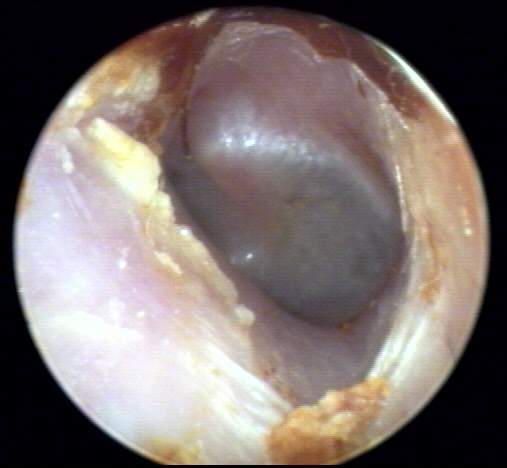

+1: Non-occlusive minor amount present but significant by location and texture to interfere with probe tube microphone measurements but not with ear-insert measurements [e.g. immittance or OAE] or hearing instrument use. Impact on impression-taking accuracy will vary with hearing instrument morphology; i.e. non-occluding full concha ITE vs. deep canal CIC. Tympanic membrane may be essentially visualized. Removal optional. EXAMPLES:+1/A(21k) | +1/B(22k) | +1/C(22k) | +1/D(18k)